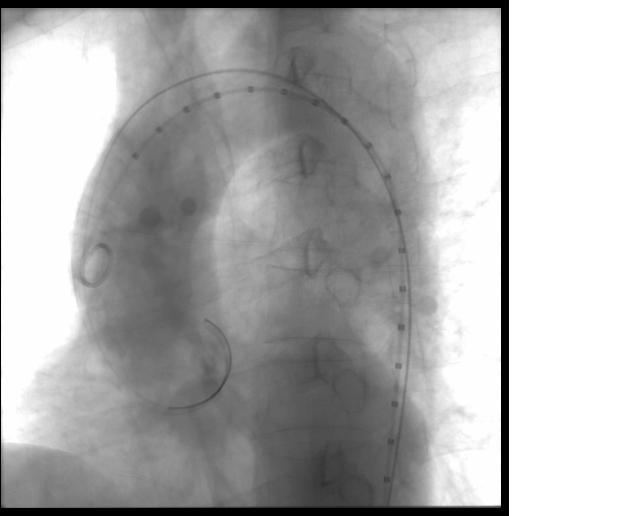

EVAR